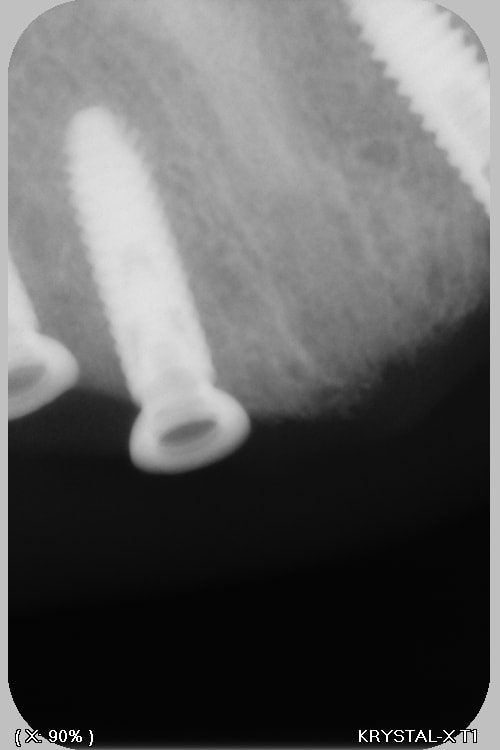

Si tu peux me donner la marque, et le type ça a été posé à Paris (2018?) Dentiste DCD, papiers perdu patiente 85 ans, adressé par un confrère qui pensait à des anthofit, mais ....

Bah, tu fatigues pxav? c'est pas des axiom reg avec ces piliers miltiunits comme ceux des TL????

Ces implants donnent le mal de mer !!! (cf pano !)

au départ je cherchais des Antogyrs , mais mon hésitation, est due au fait que (malgré mon stock de clé) je n'ai rien trouvé pour dévisser le multi unit...Bizarre, vous avez dit bizarre

C'est de l'Anthogyr avec des piliers InLink

Il faut utiliser le tournevis Anthogyr pour accès angulé (tête boule)

Effectivement, c'est le seul truc que je n'utilise pas chez eux...c'est très ingénieux, mais dans le cas présenté, ils ont tous cassés..., j'attends de voir la prothèse d'origine pour savoir d'où vient le soucis.